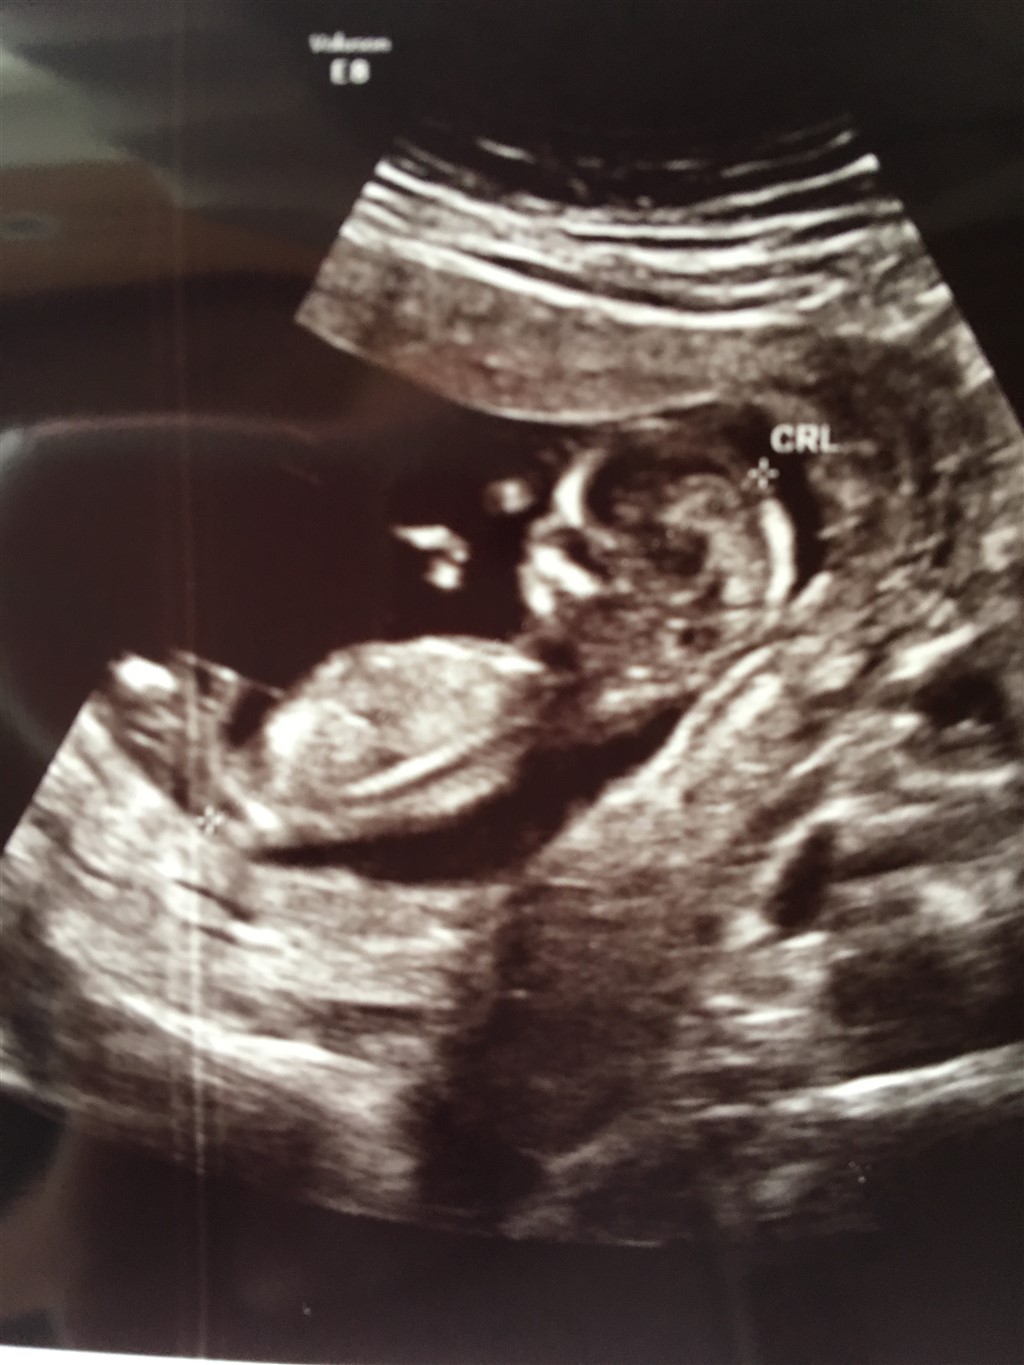

Jeg er simpelthen så glad. Havde en perfekt nakkefoldsscanning i dag. Meget lav risiko på 1:18.728 og lægen sagde det ikke kunne se pænere ud det hele! Blev rykket lidt frem i termin, så jeg har termin 29/11 fremfor 1/12  så er i dag 13+1

vedhæfter lige billede så folk kan gætte på kønnet billedet er dog ikke helt så godt.